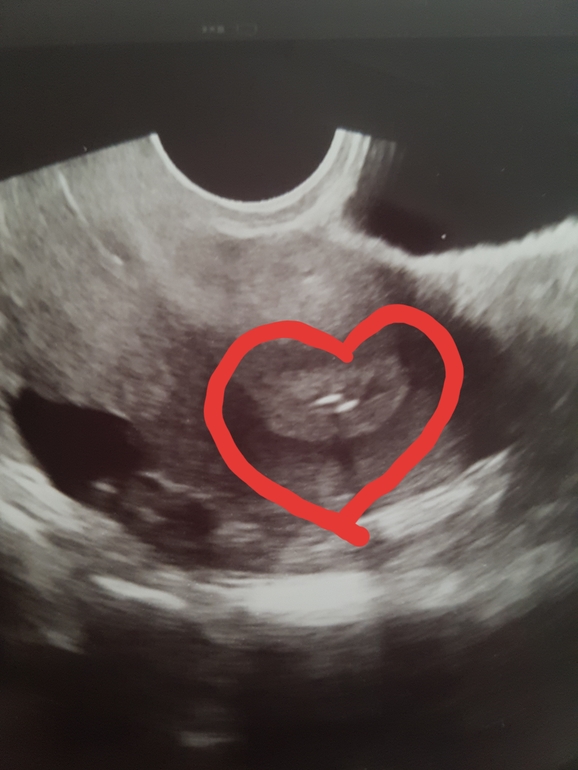

Протоколы ЭКО (Все о них, все об этом периоде+Гиперстимуляция)Всем привет, забрала нашего крошку-криошку😊 Все прошло замечательно 🙌🏻 Ничего не тянет, не болит, не колит ✊🏻 Очень сильно расстрогадась после беседы с эмбриологом, говорит малыш сильный, шансы велики, а я ее слушаю и слезы градом, толи от облегчения, толи от умиления - не понятно, дали валидол 😊😂 Эмбриошика сфоткали и вручили мне первую фотокарточку, я говорю - 100% мальчик 👶🏻 Вам фотку не покажу - я жжжжадина 😂 но..в конце переноса сделали скрин с Узи, а там...две полоски. Мой Ре сказал, что это фирменный перенос, к пузатости) зацените красоту)

И У меня вчера - мой малыш между двумя полосками😍Надеюсь и верю в своего сынулю🙏❤❤❤